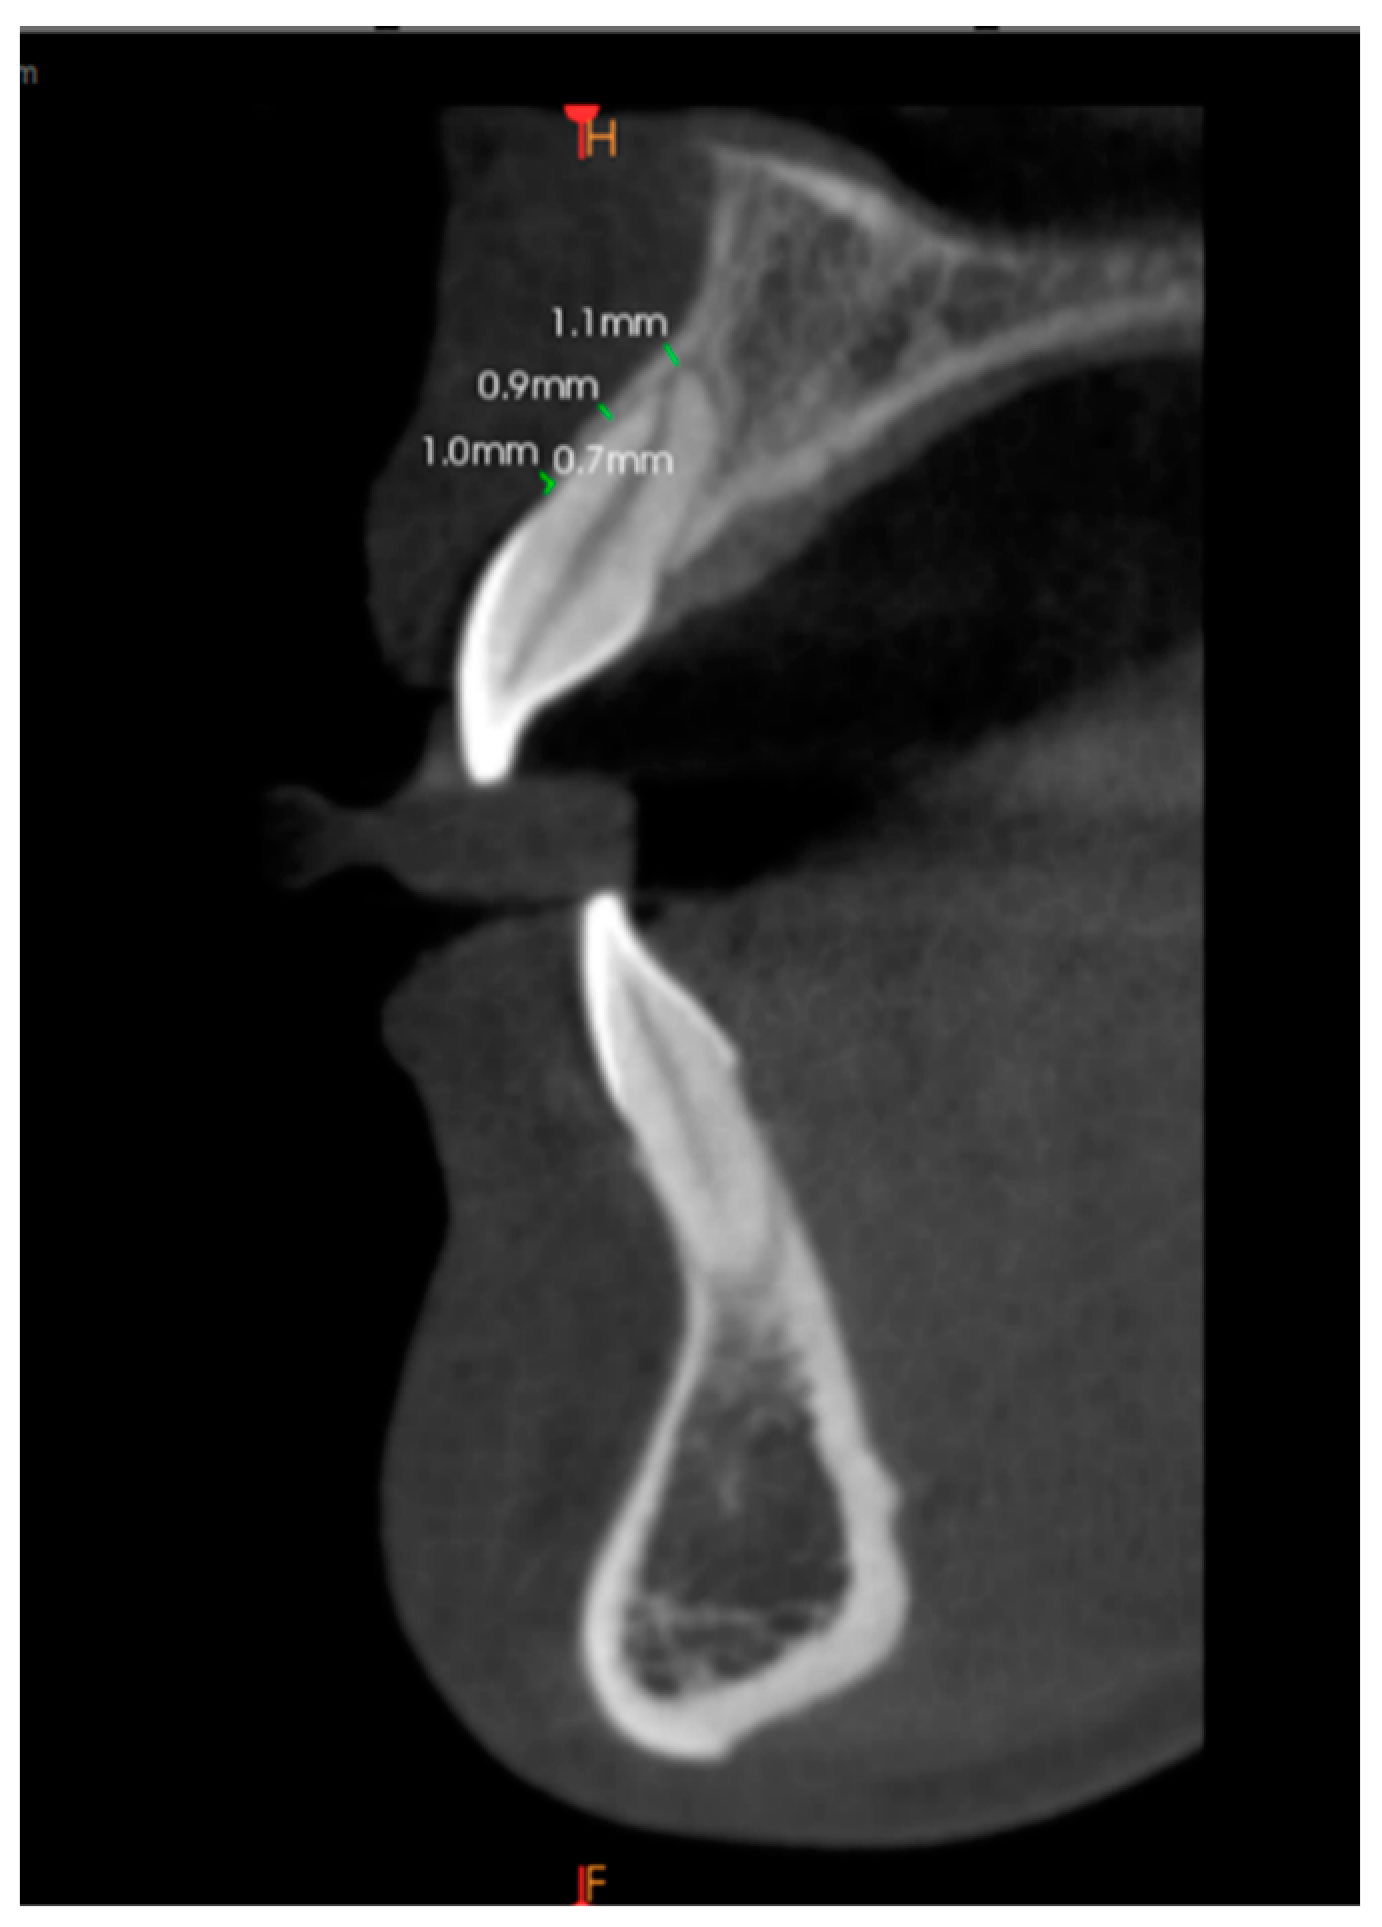

Alveolar Bone Thickness Measurement